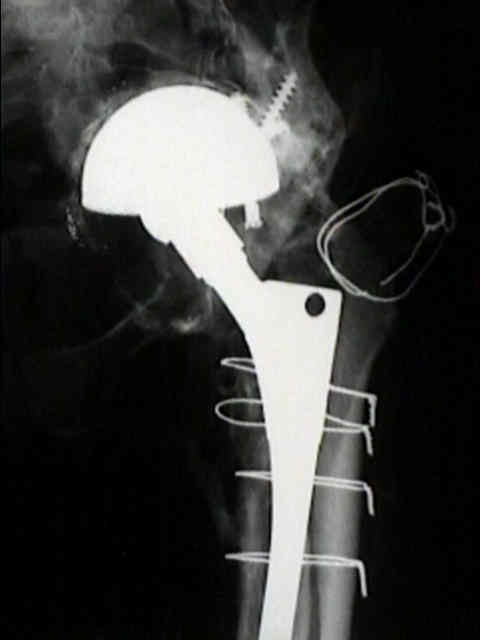

risk factors for loosening

- as noted by Kobayashi S, et al (1997), the most important factor for loosening is rapid wear of the polyethylene (more than 0.2 mm per year), followed by atrophic osteoarthritis (DJD w/o osteophytes);

definite loosening

- migration of component of more than 5 mm;

- crack in cement mantle;

probable loosening

- continuous radiolucent line > 1-2 mm wide at the bone cement interface;

- as pointed out by Hodgkins et al 1988, the finding of a continuous radiolucent line about the acetabular component indicates loosening in 94% of patients;

possible loosening

- non circumferential radiolucency which extends at least 50% around the bone cement interface;

implications of loosening

- even w/ radiographic loosening, only 10% of these hips will require revision;